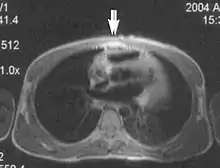

Flow can manifest as either an altered intravascular signal (flow enhancement or flow-related signal loss), or as flow-related artifacts (ghost images or spatial misregistration). Flow enhancement, also known as inflow effect, is caused by fully magnetised protons entering the imaged slice while the stationary protons have not fully regained their magnetization.[1] The fully magnetized protons yield a high signal in comparison with the rest of the surroundings. High velocity flow causes the protons entering the image to be removed from it by the time the 180-degree pulse is administered. The effect is that these protons do not contribute to the echo and are registered as a signal void or flow-related signal loss (Fig. 2).[1] Spatial misregistration manifests as displacement of an intravascular signal owing to position encoding of a voxel in the phase direction preceding frequency encoding by time TE/2.The intensity of the artifact is dependent on the signal intensity from the vessel, and is less apparent with increased TE.[1]